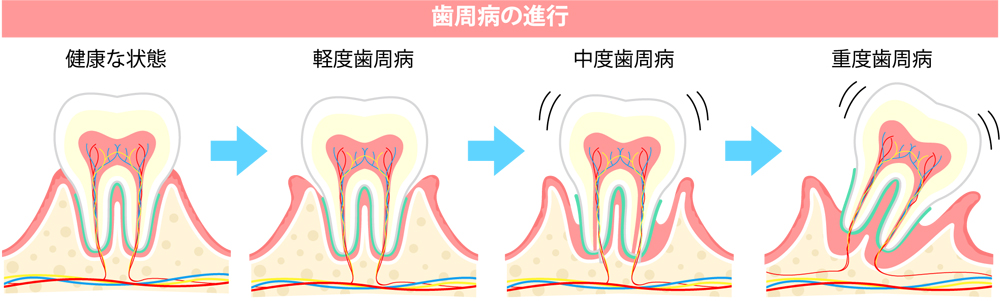

奥歯がグラグラする症状の進行段階

奥歯のグラつきは、いきなり悪化するわけではなく、段階的に進行していきます。

歯を守るためにそれぞれの段階で適切な対応を行うことが、大切なポイントです。

【軽度】 違和感や軽い動揺が出る段階

この段階では、見た目には大きな変化がなく、気づきにくいことが多いのが特徴です。

噛んだ時の少し奥歯に違和感がしたり、朝起きた時に奥歯に重さを感じたりする場合があります。

歯を支える骨や歯ぐきへのダメージはまだ軽度で、早期に治療を始めれば、症状の改善や進行の抑制が期待できる状態です。

【中度】 グラつきが現れる段階

症状が進行すると、硬い食べ物を噛むと痛みや不安定さを感じたり、指で触ると歯が動くのがわかったりするなど、日常生活の中でも動揺を自覚しやすくなります。

この段階では、歯周病が進行し、歯を支える骨の吸収がある程度進んでいる状態です。

早急な歯周病治療や噛み合わせの調整が必要になります。

【重度】 抜歯が検討される段階

さらに進行すると、歯を残すことが難しくなるケースも出てきます。

歯の動揺が強く、しっかり噛むことができない場合や膿が出る、痛みや腫れを繰り返す段階では、歯を残すことが困難と判断され、抜歯をしなければいけない場合もあります。